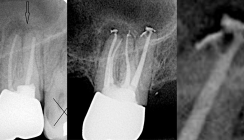

Nach Leitungsanästhesie mit Septanest 1 : 100.000 (Septodont) und Isolierung unter Kofferdam (Hu-Friedy) wurde die Krone mit einer Hartmetallfräse trepaniert. Der intrakoronale Kompositaufbau wurde mit sogenannten Endo­Tracer H1SML-Langschaftrosenbohrern (Komet Dental) unter OPMI (Leica) vorsichtig zur Vermeidung einer interradikulären Perforation soweit reduziert, dass sich die Kanaleingänge darstellen ließen. Die aus Guttapercha bestehende alte Wurzelfüllung wurde mit Hedström­feilen ISO 25 und ISO 30 entfernt. Im Anschluss erfolgte die Bestimmung der initialen Arbeitslänge mit K-Feilen und Hedströmfeilen ISO 10 mit dem Endometriemodul des VDW.GOLD-­Endomotors (VDW). Die Arbeitslänge wurde mit einem Zahnfilmröntgenbild überprüft (Abb. 3). Nach Spülung mit NaOCl 3 % wurde der Gleitpfad manuell mit K-Feilen ISO 15 und maschinell mit ProGlider-Feilen (Dentsply Sirona) kathederisiert. Die maschinelle Aufbereitung wurde mit RECIPROC®-­Feilen R25 (VDW) mesial und R40 distal vorgenommen. Im Anschluss erfolgte die passive ultraschallaktivierte Spülung mit dem Ultraschallgenerator VDW.ULTRA (VDW) mit Zitronensäure 18 % und NaOCl 3 % mit wenig Druck, um ein Überpressen des Spülmediums in den Mandibularkanal zu vermeiden. Als medikamentöse Einlage wurde die Ca(OH)2-Paste AH Temp (­Dentsply Sirona) verwendet und die Kavität mit DuoTEMP (COLTENE) und Venus Flow universal (Heraeus Kulzer) auf ­einem Wiederlager aus Teflonband ­verschlossen.

Der Patient stellte sich urlaubsbedingt erst nach sechs Wochen beschwerdefrei zur Wurzelfüllung vor. Nach Leitungsanästhesie mit Septanest 1 : 100.000 und Isolierung unter Kofferdam wurden der provisorische Verschluss entfernt und die Kanäle passiv ultraschallaktiviert mit NaOCl 3 % und Zitronensäure 18 % gespült. Nach erneuter endome­trischer Kontrolle der Arbeitslänge wurden die Mastercones eingepasst und röntgenologisch kontrolliert (Abb. 4). Die apikale Läsion erscheint deutlich verkleinert. Die Wurzelfüllung erfolgte thermoplastisch in vertikaler Kompaktion mittels BeeFill® 2in1 (VDW) mit dem Sealer AH Plus (Dentsply Sirona). Die Röntgenkontrolle zeigt etwas überpressten Sealer im Bereich der distalen Wurzel (Abb. 5). Auf der 3-Monats-Kontrollaufnahme (Abb. 6) ist ein gleichmäßig durchgehender Parodontalspalt zu sehen. Die apikale Parodontitis scheint komplett ausgeheilt, der überpresste Sealer teilweise resorbiert.